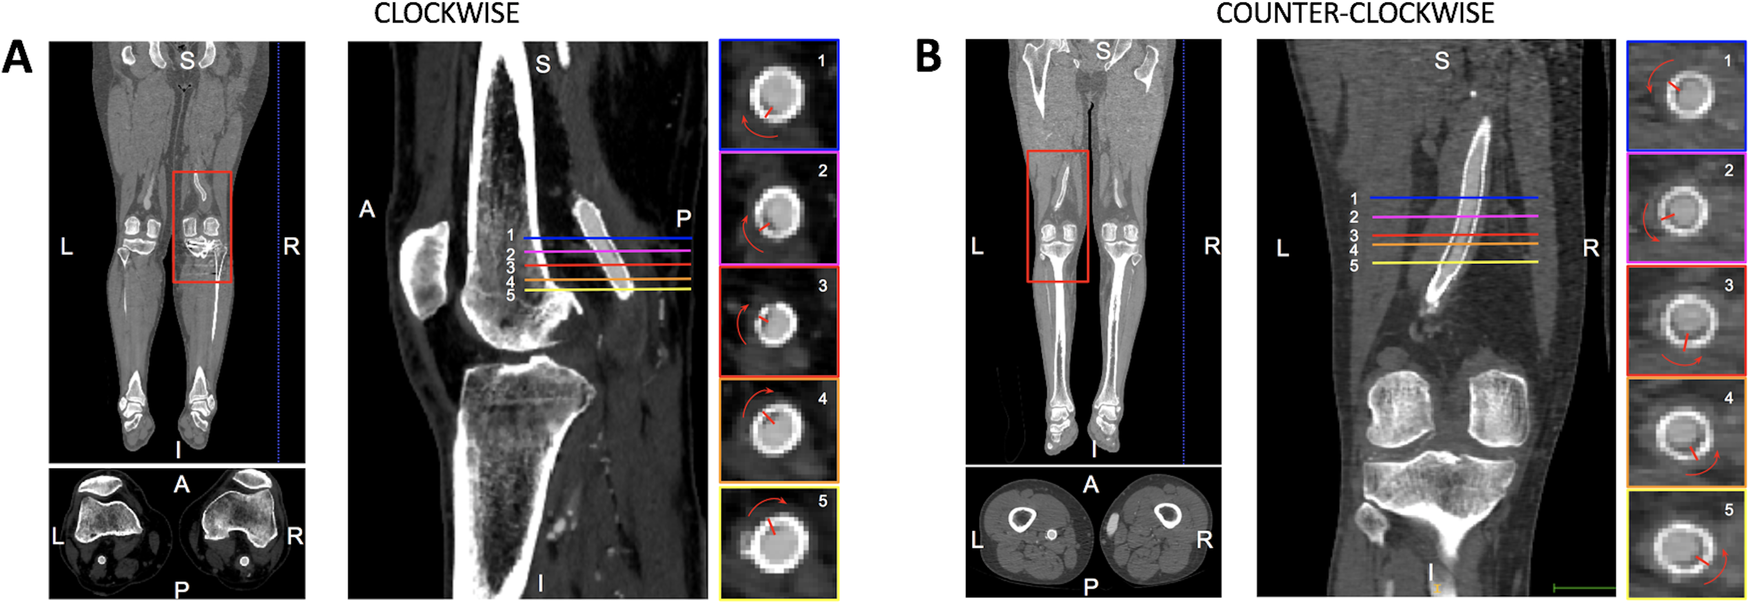

The spiral shape of the stent-graft thrombus was assessed through a visual inspection of CTA images and 3D surfaces by an expert radiologist. The direction of rotation of EMTS was assessed in each CTA image by analyzing the CTA slices from top to bottom and categorized as clockwise or counterclockwise, as shown in Figure 1.

Figure 1

Illustrative representation of the CTA analysis to assess the helical shape of the thrombosis and its rotation along the femoropopliteal axis. This is an analysis of the right leg showing a clockwise rotation of the thrombosis as the axial slices shift from top (1) to bottom (5).

An analysis of the shape of the thrombotic apposition revealed the presence of portions of thrombosis with a helical shape in 8/13 (61.5%) patients, a counterclockwise rotation in 4/5 (80%) of patients with stent-grafts in the left leg, and a clockwise rotation in 3/3 (100%) patients treated in the right leg. The results for single patient cases are reported in Supplementary Table S2.